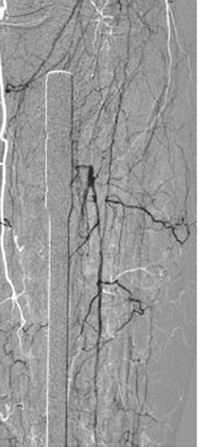

Resultado tras la activación del catéter Xpeedior® de AngioJet® durante 160 s (técnica Rapid Lysis con Alteplase) que muestra la arteria poplítea patente y la estenosis crítica de la arteria peroneal.